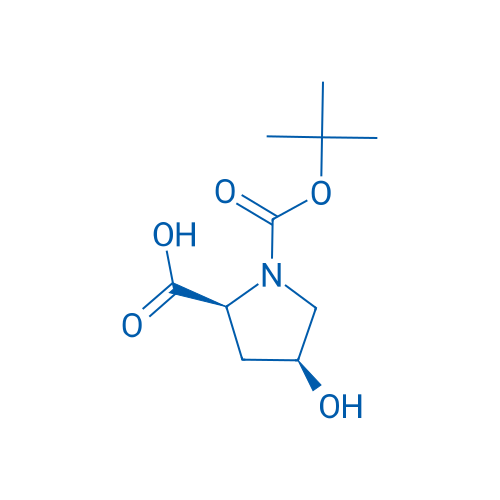

AS23580 Wakizashi: Heki Mitsuhira Zo(NBTHK Hozon Token)(Token Kenkyu Rengokai estimation paper) – 日本刀販売の葵美術, 87691-27-8|(2S,4S)-1-(tert-Butoxycarbonyl)-4-hydroxypyrrolidine-2-carboxylic acid|BLD Pharm,

87691-27-8|(2S,4S)-1-(tert-Butoxycarbonyl)-4-hydroxypyrrolidine-2-carboxylic acid|BLD Pharm, AS24696 Wakizashi: Omi no Kami Fujiwara Tsuguhira (NBTHK Hozon Token) – 日本刀販売の葵美術